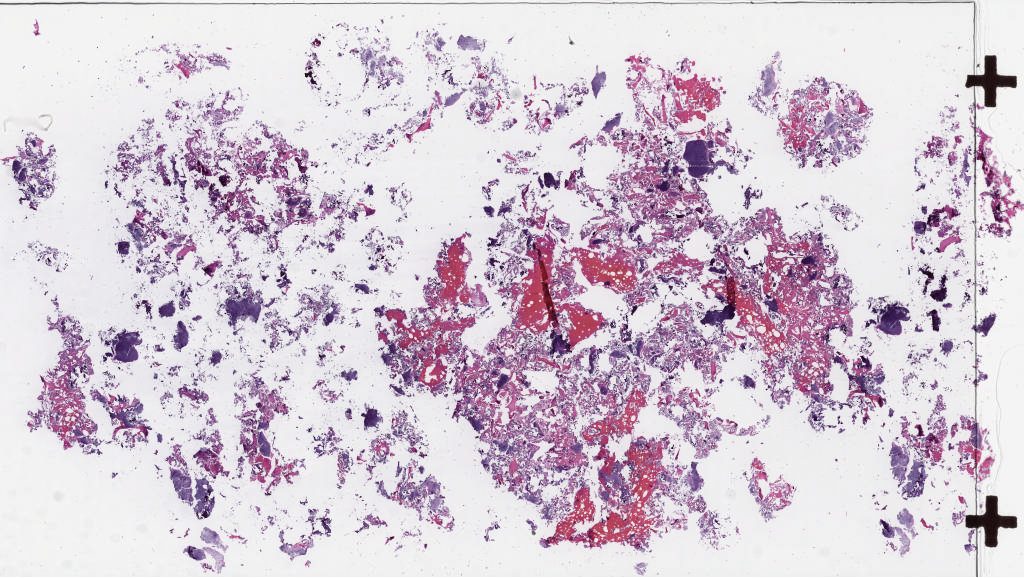

Case3.svs

161352

x

90965

@

40X